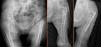

La presencia de unos abductores de cadera debilitados (degeneración grasa) originó un cierto grado de inestabilidad intraoperatoria en 3 pacientes. En uno de ellos, tras la reducción del implante de prueba, se observó una clara inestabilidad al colocar el vástago en su posición anatómica. En la planificación preoperatoria no se incluyó ni un vástago largo ni un implante restrictivo, de forma que el vástago femoral se cementó en posición superior para obtener una mayor tensión de partes blandas y una reducción estable (fig. 1 A-C).

En el primero, una fractura femoral periprotésica (Vancouver B1) precisó fijación con una placa larga preconformada. Como complicación, durante la manipulación del miembro presentó una fractura iatrogénica transversal, puenteada por la placa (fig. 1 D-H)